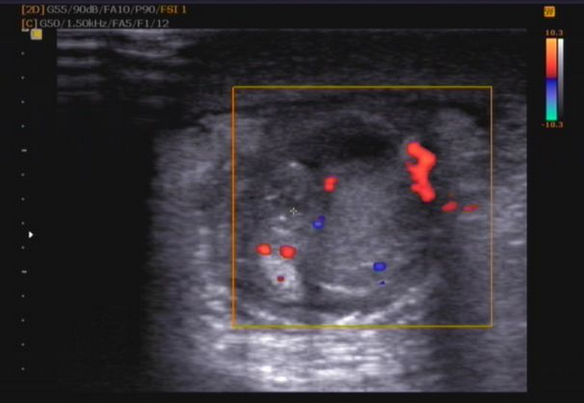

睾丸破裂主要是由于外伤一起的,具体还可表现为睾丸疼痛、睾丸肿胀、睾丸脱位等,对男性来说要遭受很大的痛苦,治疗不及时的话甚至影响到性功能和生育能力。那么睾丸破裂怎么办?具体症状是什么?

1、睾丸破裂时睾丸肿胀,硬,剧痛与触痛。

2、睾丸破裂会有睾丸脱位的症状,睾丸被挤压到阴囊以外的部位。如腹股沟管,股管、会阴等部位的皮下,局部剧痛、触痛、痛侧阴囊空虚。

3、睾丸破裂时阴囊皮肤瘀斑,血肿,开放性损伤阴囊撕裂,睾丸外露。

4、睾丸破裂时会有剧疼甚至昏厥,阴囊血肿,触痛明显,睾丸轮廓不清。